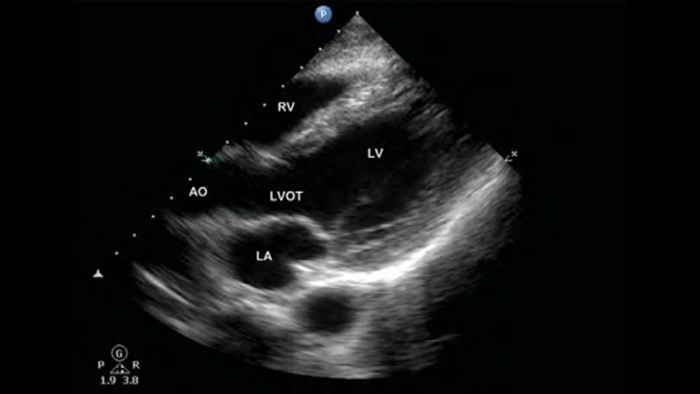

• Interval de frecvenţă de operare extinsă cuprins între 4 şi 1 MHz • Imagistică 2D, Doppler color, M-mode, XRES avansată şi armonică multivariată • Imagistică de înaltă rezoluţie pentru aplicaţii abdominale şi cardiace: optimizări ale presetărilor de imagistică cardiacă, OB/GYN, pulmonară, abdominală şi FAST

De la dezvăluirea detaliilor fine ale unei imagini până la vizualizarea de înaltă definiție a ţesutului îmbogăţit din mai multe unghiuri, Lumify vă poate ajuta să luaţi decizii în timp real cu mai multă încredere, de la evaluare până la recuperare.